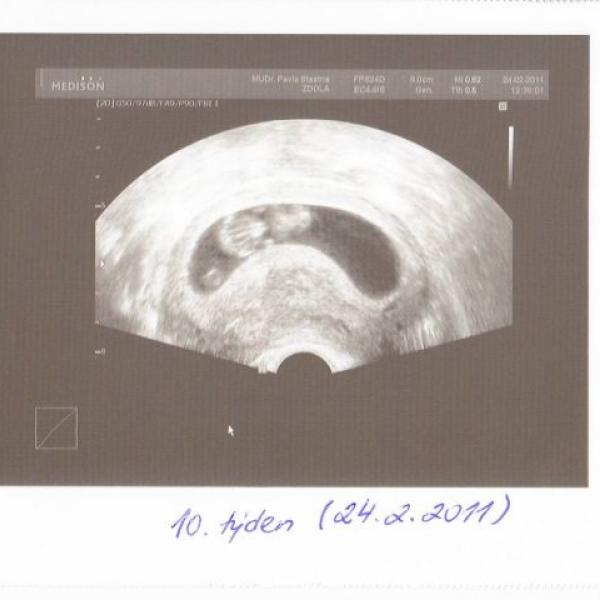

tak jsem minulý týden absolvovala první UTZV a přikládám fotku našeho broučka - měří 3,8cm a má se čile k světu, srdíčko buší jak o závod :dance: :€p€: Na nevolnosti jsem dostala čípky TORECAN a musím uznat, že je mi o něco lépe, zvracení se zmenšilo na 2x denně, tak je to paráda!!! Přeji všem těhulkám, aby se měly fajn a hlavně zdravě! pááá :\x: